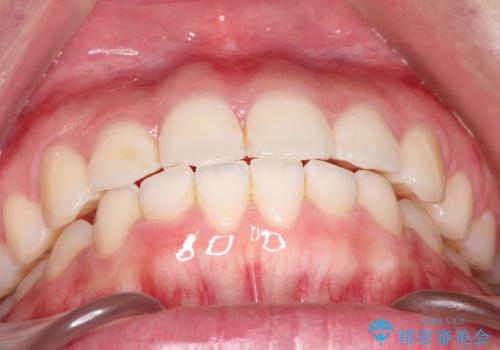

【インビザライン】前歯が出ているのを治したい

- 前歯が出ていることを主訴に来院されました。

前歯の突出感が改善され、満足していただきました。